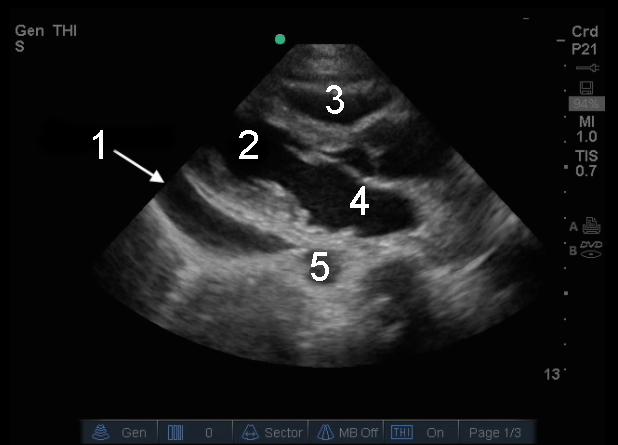

Heart Parasternal Long Axis (PLAX) Pericardial Fluid Image

1. Pericardial Effusion (Fluid)

2. Left Ventricle (LV)

3. Right Ventricle (RV)

4. Left Atrium (LA)

5. Aorta (Ao)